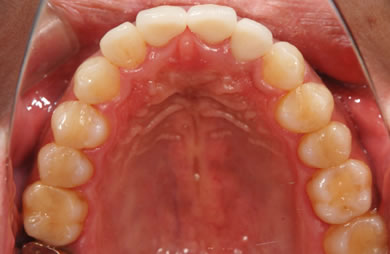

セラミックの症例写真 SHINBI

セラミック治療

| 性別/年齢 | 男性 / 29歳 | ||||||||||||||||||||||||||||||||

| 主訴 | 歯並びを綺麗にしたい。奥歯の銀歯が目立つので白くしたい。 | ||||||||||||||||||||||||||||||||

| 治療方針 | 上の前歯部に関しては審美的回復の優先を切望されているため、透明感のあるオールセラミックのハイクオリティタイプを使用。 | ||||||||||||||||||||||||||||||||

| 治療内容 | オールセラミック(ハイクオリティ)3本、ハイブリッドセラミックインレー10本 | ||||||||||||||||||||||||||||||||

| 総治療費 | 714,286円 | ||||||||||||||||||||||||||||||||

| 治療期間 | 7ヶ月 |